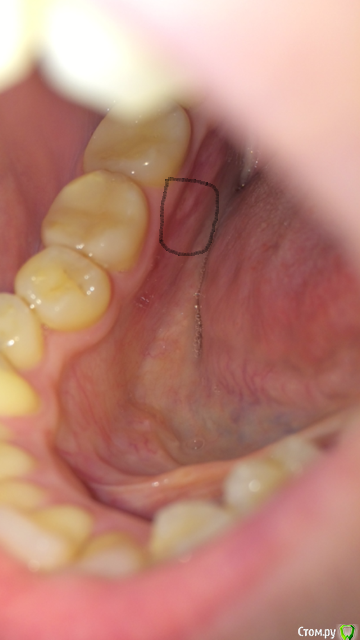

также болела область с внутренней стороны десны возле примерно  6, 7, 8 зубов справа снизу. Под 7 зубом что-то белое виднеется.

Прикладываю фото.

post-50717-0-94759300-1525732526_thumb.png